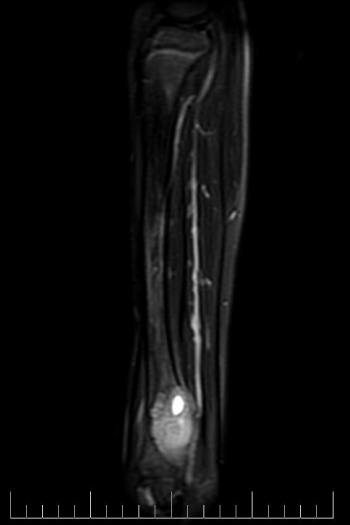

A 10-year-old female presented with left lower leg pain that had progressively increased over the duration of 1 year. On physical examination, tenderness was elicited on palpation of the distal tibia. Routine laboratory testing was normal. X-Ray was performed and revealed a lytic lesion with sclerotic margins in the left lower tibia (Figure 1). MRI was subsequently performed, demonstrating a left lower tibia lesion with low signal intensity on T1 weighted images (Figure 2), and high signal intensity on T2 weighted images (Figure 3). Pathology of the tumor revealed a diagnosis of a CMF. She was treated with curettage and autologous bone grafting (Figure 4). Post op eratively the left leg was immobilized with a plaster cast with restricted weight bearing (Figure 5). Follow up X-ray after 5 years demonstrates no tumor reoccurrence (Figure 6, Figure 7).

Figure 2: MRI sagittal T1 of the left tibia.

MRI demonstrates low signal intensity on T1 weighted images (Figure 2, Figure 11 and Figure 12). T2 weighted images demonstrate high signal intensity (Figure 3, Figure 13). Post gadolinium contrast T1 weighted sagittal view demonstrates diffuse heterogenous enhancement (Figure 14). Post gadolinium contrast T1 weighted axial view demonstrates peripheral nodular enhancement (Figure 15).